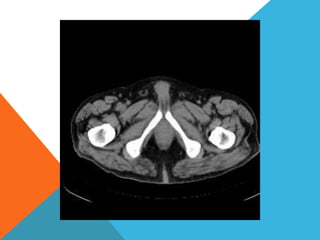

El paciente presentó síntomas de sangrado digestivo y pérdida de peso. Exámenes revelaron gastritis crónica asociada a H. pylori. Un tumor fue descubierto en una colonoscopia normal. La cirugía removió un tumor fibroide solitario, una rara neoplasia mesenquimal que usualmente crece lento y tiene bajo potencial de malignidad. El pronóstico después de la remoción quirúrgica es generalmente bueno.